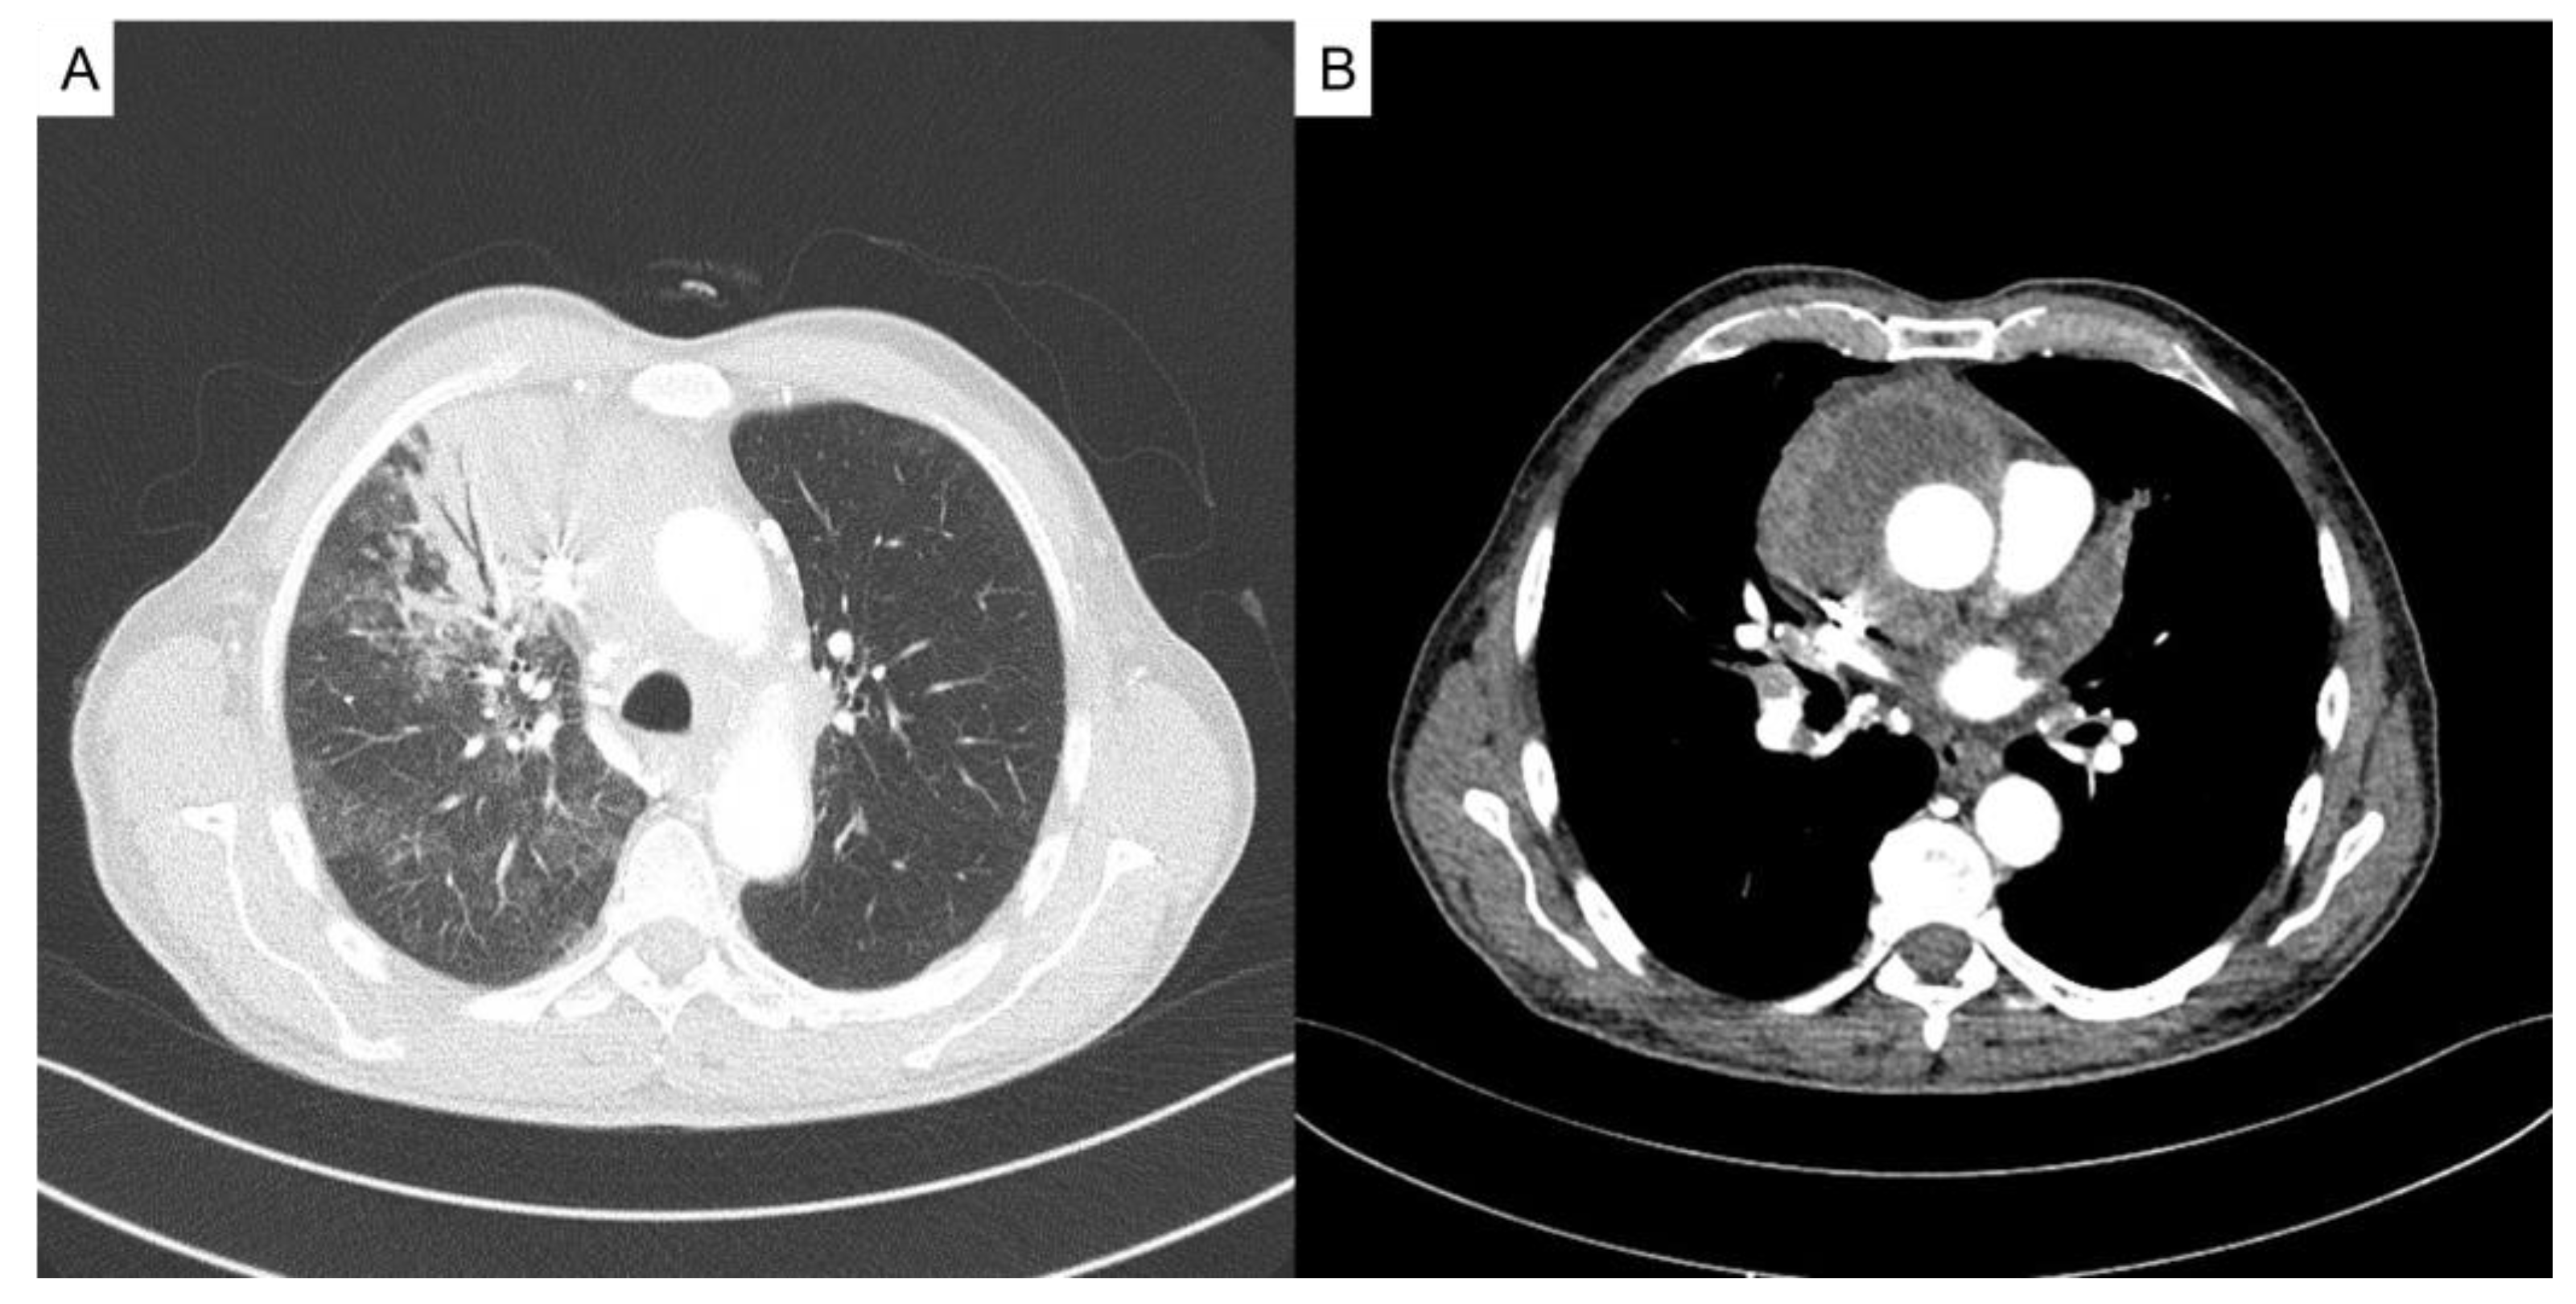

A 63-year-old man, previously healthy and living in a rural area, presented with a 5-month history of hemoptysis, pleuritic pain, weight loss of 14 kilograms, and night sweats. One month before admission he had been diagnosed initially with community-acquired pneumonia at his local hospital however, no information about the treatment was available. At admission, the patient was in poor general condition with tachycardia, fever, and tachypnea. Physical examination revealed no abnormalities in the cardiopulmonary and skin exam. The initial investigation showed a high C-reactive protein (10.74 mg/dL; reference range: 0-0.3 mg/dL), leukocytosis (21,800/mm3; reference range: 5,000-10,000/mm3), neutrophilia (19,900/mm3; reference range: 4,000-7,000/mm3), and a chest X-ray with parenchymal consolidation in the right upper lobe and poorly defined opacities in the middle lobe (Figure 1). A contrasted computed tomography scan of the chest showed extensive pulmonary parenchymal involvement in the right upper lobe and middle lobe and an anterior mediastinal mass with central necrosis and enhancement of its contours (Figure 2).

Figure 2. Contrasted computed tomography scan of the chest. A) Extensive pulmonary parenchymal involvement in the right upper lobe and middle lobe. B) An anterior mediastinal mass with central necrosis and enhancement of its contours.